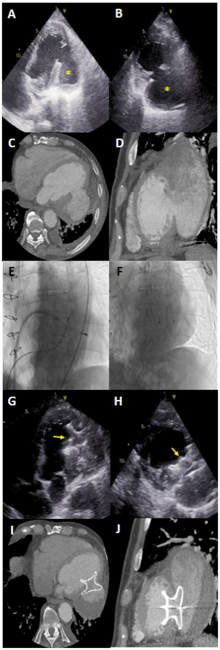

A 78-year-old male patient with a history of coronary artery disease (he had undergone coronary artery bypass surgery 4 years ago), heart failure with mildly reduced ejection fraction, diabetes mellitus, and transient ischemic attack presented to the emergency department with complaints of dyspnea (New York Heart Association Class 4) despite the optimal medical therapy. Transthoracic echocardiography (TTE) revealed a huge left ventricular inferolateral wall pseudoaneurysm filling with a leak (Figure, A and B; Videos 1-3). The size of the pseudoaneurysm neck was 36 mm, and the pseudoaneurysm was 54 x 75 mm on cardiac computed tomography (Figure, C and D). The wall of the pseudoaneurysm was fragile, and the patient was a high-risk candidate for surgical treatment of the pseudoaneurysm. Therefore, the heart team decided to close the pseudoaneurysm percutaneously.

However, there was no ventricular septal defect occluder of a suitable size for the wide neck of this pseudoaneurysm, so we decided to use an atrial septal defect (ASD) occluder. Two right femoral venous sheaths and 1 right femoral arterial sheath were placed. One femoral vein cannulation was used for coronary sinus catheter placement, which provided anatomical guidance. The other femoral vein cannulation was used for atrial septostomy. Arterial cannulation was used for the pigtail catheter to perform the left ventriculography. Left ventriculography showed the site of the pseudoaneurysm, the neck of the pseudoaneurysm, and the size and extent of the lesion (Video 4). After the atrial septostomy, the delivery sheath was moved to the left ventricular cavity. Due to the possibility of pseudoaneurysm wall rupture, an ablation catheter was used instead of a guidewire to carry the sheath. The ablation catheter was easily guided to the neck of the pseudoaneurysm, and the sheath was advanced safely through this catheter (Figure, E; Video 5). A 38-mm Amplatzer ASD occlude (Abbott) was deployed into the pseudoaneurysm, ensuring the left atrial disc was deployed in the pseudoaneurysm and the right atrial disc was deployed in the left ventricle (Figure, F; Video 6).

After the procedure, TTE confirmed the closure of the pseudoaneurysm, and the patient was discharged the next day (Figure, G and H; Videos 7 and 8). At 6-month follow-up, the patient was not admitted to the hospital due to decompasated heart failure, and control cardiac computed tomography revealed the ASD device was in the proper position and the pseudoaneurysm had shrunk (Figure, I and J).